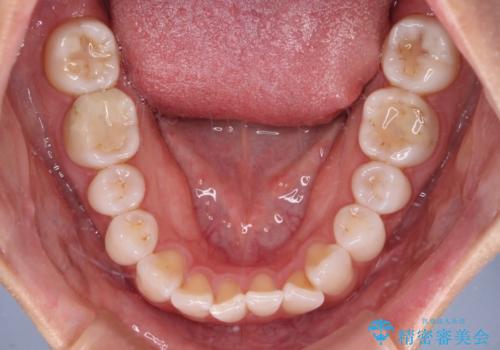

【モニター】前歯のデコボコと小さい前歯 インビザライン矯正とオールセラミッククラウン補綴治療

- 前歯の歯並びと生えてきたときから小さい前歯を気にして来院された患者様です。

上下前歯の歯列不正はインビザラインにより整え、その後に、矮小歯の前歯をオーダーメイドタイプのオールセラミッククラウンにて補綴治療することとしました。

セラミッククラウンにて大きさを変更することを前提に矯正治療を開始したため、大変満足のいく仕上がりとなりました。